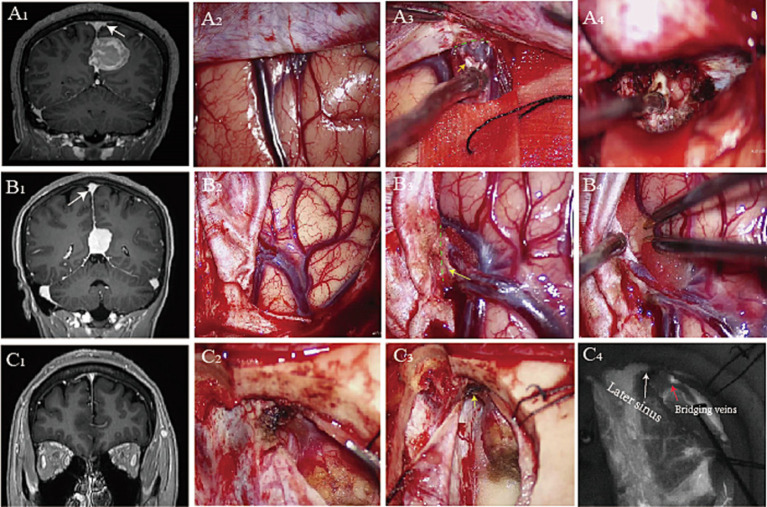

Damage to bridging veins could lead to disastrous complications during interhemispheric approaches. We investigated the morphological and histological characteristics of bridging veins. A total of 10 cadaveric heads and 86 patients were analyzed with either anatomic dissection or neuroimaging. The morphological features of the bridging veins and superior sagittal sinus were analyzed by the endoscope. The histology of the junction between the bridging veins and superior sagittal sinus was evaluated under the microscope with staining for H&E, elastic fiber, and Masson's staining. We found three types of bridging vein configurations in the junction between the bridging vein and superior sagittal sinus: direct connection (type A), vein runs a certain distance below the dural wall tightly (type B), and vein runs a certain distance on the lateral sinus (type C). Valvular-like fibrous cords were present on the opening of type A, trabecular in type B, and arachnoid granules in type C. Loose connective tissue connected the venous wall and dura mater in type A, sinus wall forms the inner wall of the bridging vein in type B, bridging vein accompanied by arachnoid granules in the type C. This classification enables surgeons to predict various bridging vein configurations, followed by safely achieving the optimal dissection during interhemispheric approaches.

在半球间入路过程中,桥接静脉的损伤可能会导致灾难性的并发症。我们研究了桥接静脉的形态学和组织学特征。我们通过解剖学解剖或神经影像学检查分析了 10 具尸体头部和 86 位患者。通过内窥镜分析了桥接静脉和上矢状窦的形态特征。在显微镜下对桥接静脉和上矢状窦交界处的组织学进行评估,并进行 H&E、弹性纤维和 Masson 染色。我们在桥接静脉和上矢状窦交界处发现了三种桥接静脉构型:直接连接(A 型)、静脉紧贴硬脑膜壁下方一定距离(B 型)和静脉在侧窦上一定距离(C 型)。A 型的静脉壁和硬脑膜之间由松散的结缔组织连接,B 型的窦壁构成桥接静脉的内壁,C 型的桥接静脉伴有蛛网膜颗粒。这种分类方法使外科医生能够预测各种桥接静脉的构型,从而在半球间入路时安全地实现最佳解剖。